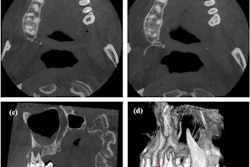

Since the distobuccal canal was not located in its usual location and a canal was seen in an unusual place between the buccal and palatal canals, a limited field of view cone-beam computed tomography (CBCT) scan was taken. The 3D images of the maxillary second molar revealed that the buccal and palatal roots in the coronal and middle third region of the root were fused. However, they were separated apically.

(A-C) Axial CBCT images in the cervical, middle, and apical region of the man’s molar. (D) The coronal section showed the apical split of roots and early periapical radiolucency in the palatal root (red arrow). (E) The sagittal section shows the gouging of the floor.

Also, the CBCT images confirmed that the distobuccal canal was adjacent to the palatal orifice. The scan further revealed that the coronal section of the tooth had early periapical radiolucency in the palatal root, which was not visible on the early images, the authors wrote.